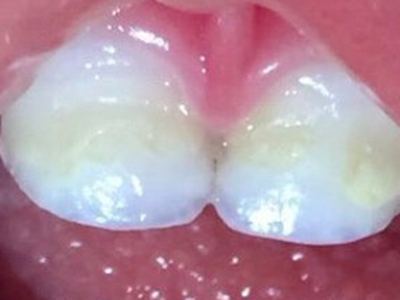

牙釉质发育不全牙齿白斑图

牙釉质发育不全患者可以仅仅出现牙齿色泽和透明度的改变,形成白垩色釉质,即类似于牙齿上有白斑,此时牙冠形态通常较完整。